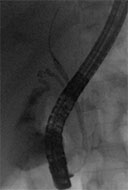

The common bile duct was accessed using a Jagtome™ RX 39 Cannulation Sphincterotome, and a balloon-occluded cholangiogram was performed (Fig. 1). The cholangiogram displayed a large filling-defect at the bifurcation, with no dye in either of the hepatics. SpyGlass™ DS Direct Visualization System was sent over the guidewire, into the common bile duct (Fig. 2). Upon arrival at the bifurcation, the area was strictured. SpyBite™ Biopsy Forceps were used to extract tissue for biopsy, and pathology confirmed a diagnosis of cholangiocarcinoma. A plastic stent was placed for further patient evaluation. The patient was found to have metastatic disease and was not a surgical candidate.

Figure 1